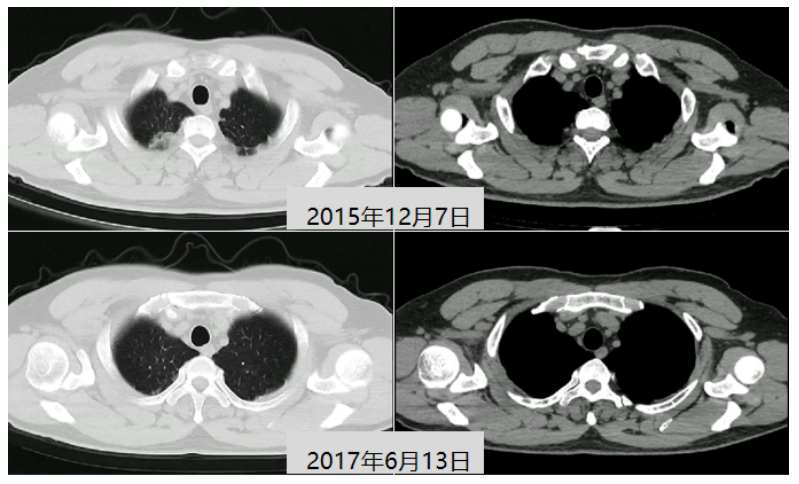

患者2015年12月7日在本院就诊时的胸部CT显示两上肺以及左肺胸膜下均有病变(图6)。追问病史。患者曾接受抗结核治疗一年半。2017年6月13日复查胸部CT显示两上肺病灶基本消失(图6),说明患者曾经感染过结核,并且抗结核治疗有效。

图片

6  患者胸部CT比较